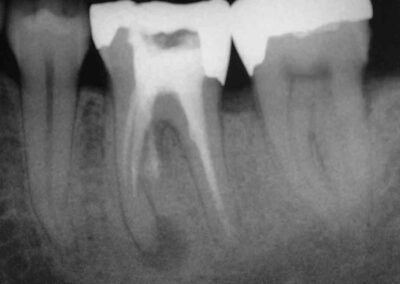

Der folgende Fall zeigt, dass eine vermutete Zyste nicht ausheilt, wenn es nicht gelingt, einen ordentlichen Zugang für das Desinfektionsmittel zu schaffen.

Der Patient stelle sich im Juni 2004 mit Aufbissbeschwerden und einer vestibulären Druckdolenz über der Wurzelspitze von 36 vor.

Ob in diesem Falle eine wirklich vollständige Ausheilung erreicht ist fraglich und bleibt abzuwarten. Wahrscheinlicher erscheint uns, dass sich nur ein momentan stabiles Gleichgewicht zwischen Angriff und Abwehr eingestellt hat. Die Zukunft wird auch zeigen, ob sich im Zusammenhang mit der via falsa interradikulär eine neue Aufhellung entwickelt, oder ob es sich um ein transitorisches Phänomen im Zusammenhang mit der deutlich fortgeschrittenen Resorption des überpressten Sealers handelt. Die dem Patienten als Alternative zum Zuwarten angebotene Hemisektion wurde vom Patienten abgelehnt. Dies zumindest so lange, wie Beschwerdefreiheit bei Belastung besteht.